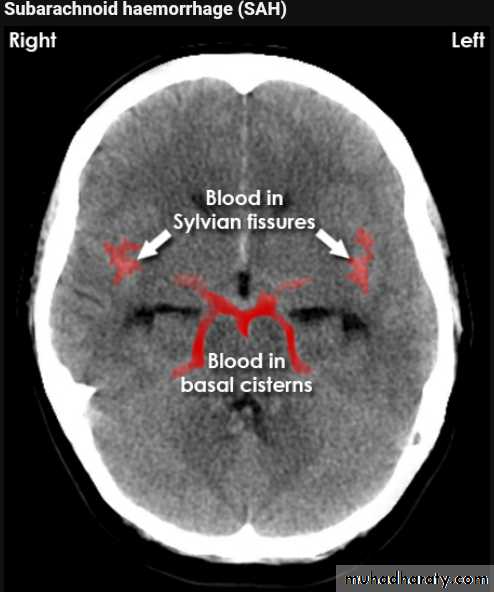

Subarachnoid hemorrhage

causesdue to ruptured aneurysm over 90 % of cases spcially at the circle of Willis .

ruptured AV malformation .

trauma .

CT finding

hyper density is seen within the SAS ( hyperdense sulci , being filled with clotted blood)

opacified inter hemispheric fissure ( become white & more dense )

opacification of the falx cerebri .

SAH

White sulciOpacified IHF